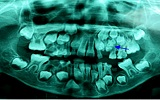

Trồng răng Implant có đau không? - hình ảnh 2

Thời gian thực hiện quá trình trồng răng implant mất khoảng 60 - 90 phút